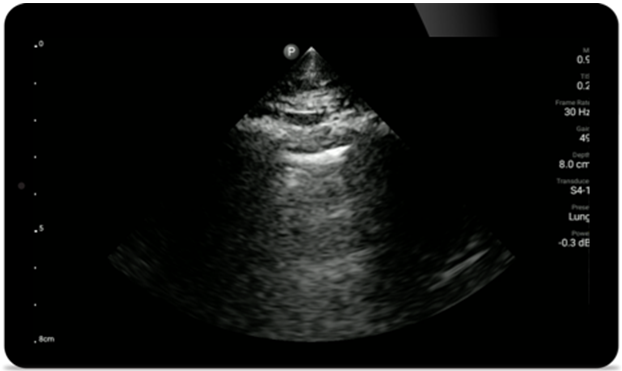

Utilizaţi Lumify pentru evaluarea căilor respiratorii şi pulmonare

Soluţiile Lumify POCUS vă pot ajuta să detectaţi tubul endotraheal, să asistaţi procedurile urgente de cricotiroidotomie, să diagnosticaţi efuziunea pleurală şi bolile alveolare interstiţiale.